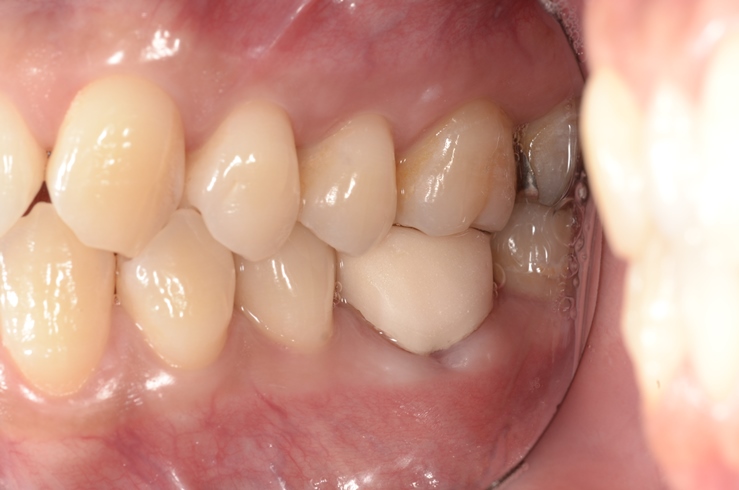

その後は、症状も特になく経過良好であることからかぶせ物を入れて終了となりました(^0^)/

終了時はこんな感じ!